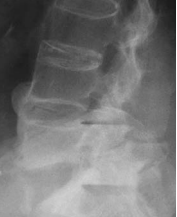

Mr O, an elderly man, was recently admitted for severe low back pain of two months duration. He had chronic low back pain on and off for many years. His pain this time was so severe that he could sit for only a short while. He could barely walk a few meters. The neurological examination was normal. X-ray of his lumbar spine revealed the feature of “’ bamboo spine’ typical of ankylosing spondylosis. There was a fracture through the ossified L5-S1 disc space which was widely opened. Flexion and extension x-ray showed there was considerable instability at the L5-S1 segment. Mr O underwent a two-stage surgery. The 1st stage was posterior L4 to S1 pedicle screw instrumentation. The 2nd stage anterior L5-S1 strut grafting with titanium mesh and fibular allografts was performed 5 days later. Post surgery, Mr O was relieved of his pain and was ambulating.

Pathology of Ankylosing Spondylitis The basic pathology of ankylosing spondylitis is inflammation followed by ossification of ligaments surrounding the spinal column. The process usually begins in the sacroiliac joint causing sacroiliitis which shows on x-ray as fizziness of sacroiliac joint. The process extends up the spine to a variable extent. At times the whole spine may be involved resulting in a completely rigid spine. The ossification of the spinal ligaments results in bone bridges across the adjacent vertebrae giving rise to the classical description of bamboo spine noted in the spinal x-ray. The ligaments surrounding the hip joints may also become ossified, resulting in stiff hips. When this occurs, patient becomes severely disabled because he will not even able to sit upright.